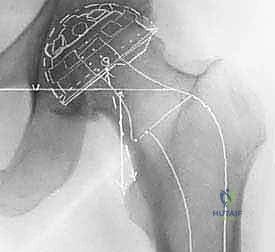

- التصوير الشعاعي الدقيق: إجراء صور أشعة سينية (X-rays) بوضعيات محددة، وفي بعض الحالات المعقدة يتم طلب أشعة مقطعية (CT Scan) أو رنين مغناطيسي (MRI) لعمل تخطيط ثلاثي الأبعاد للعملية واختيار مقاسات المفصل الصناعي بدقة متناهية.

الخطوة الثالثة: تحضير وزرع الكوب الحُقي (Acetabular Component)

في جراحة الورك الإسمنتية الكلية، يتم استخدام كوب مصنوع من البولي إيثيلين عالي الكثافة (بلاستيك طبي شديد التحمل). يتم وضع طبقة من الإسمنت العظمي داخل التجويف الحُقي، ثم يُضغط الكوب البلاستيكي بقوة في الزاوية الميكانيكية الصحيحة. يتصلب الإسمنت خلال دقائق ليصبح جزءاً لا يتجزأ من الحوض.

الخطوة الرابعه: تحضير القناة الفخذية وزرع الساق المعدنية (Femoral Stem)

يتم استخدام مبارد جراحية خاصة لتجويف وتشكيل القناة الداخلية لعظمة الفخذ. بعد تنظيف القناة وتجفيفها، يتم حقن الإسمنت العظمي السائل داخل القناة الفخذية. فوراً، يقوم الدكتور هطيف بإدخال الساق المعدنية (Stem) المصنوعة من سبائك التيتانيوم أو الكوبالت كروم داخل القناة المملوءة بالإسمنت. يتم تثبيت الساق في الموضع الدقيق حتى يتصلب الإسمنت تماماً، مانعاً أي حركة دقيقة مستقبلاً.